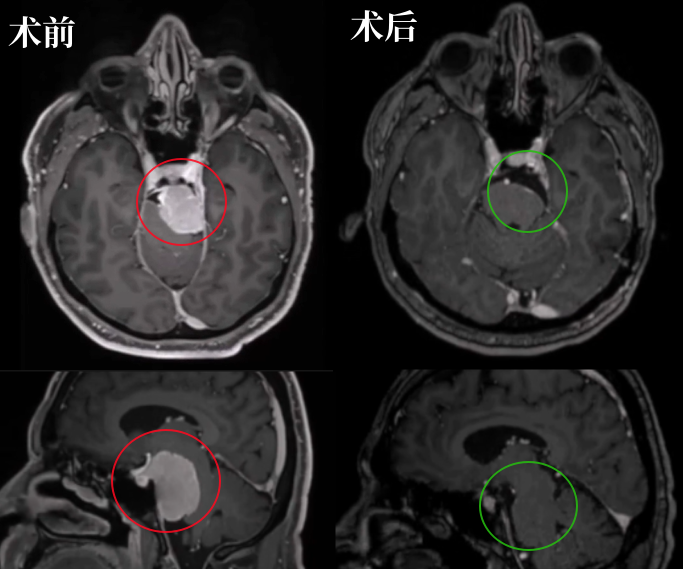

先来看看这个案例,29×39×38 mm,一个大型岩斜区脑膜瘤像一个小山丘一样,山顶直接挤压“生命禁区”脑干,还与神经血管结构紧密粘连。此时的他仅有头痛症状。

要知道,岩斜区这个位置的脑膜瘤,大小每增加1cm,手术难度就升级。位置凶险,肿瘤大,很多人以为肯定得开颅才能切干净。

其实不然,在INC福教授的定制化手术策略之下,无需开颅,仅右侧单鼻孔入路便全切肿瘤。脑干复位良好,未见脑脊液漏及新发神经功能障碍。